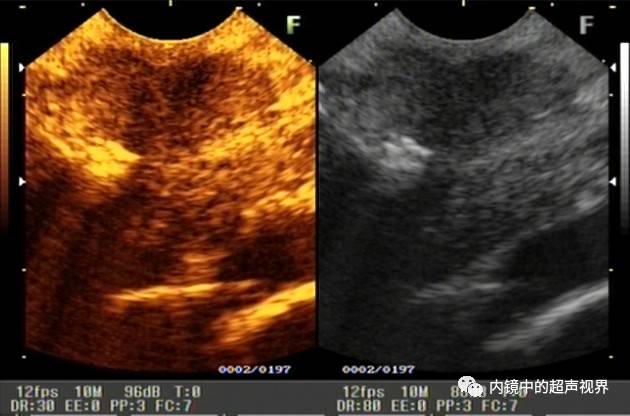

再来一张间质瘤的图片,也是DR30和80的对比。

有没人觉得,这个间质瘤的图片跟前面两个病灶不太一样,似乎感觉高DR模式看起来更舒服,那是因为,间质瘤为低回声,它周围的软组织为高回声,本身就能形成良好的对比,无需降低DR,而高DR模式更显细腻。